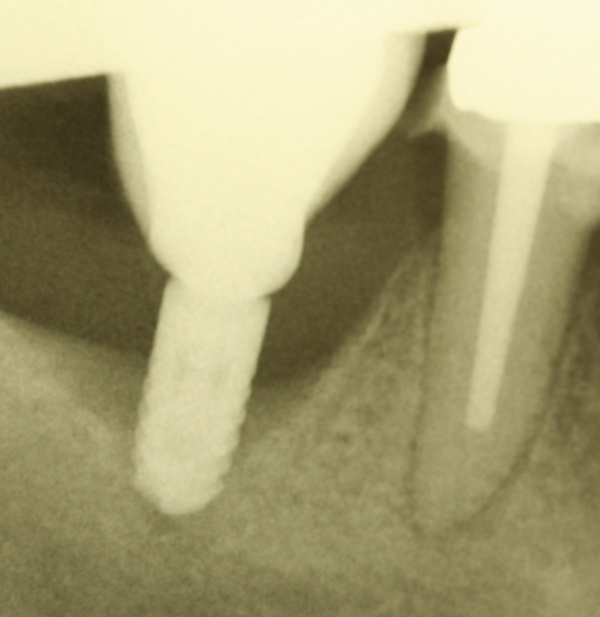

Dies lässt sich exemplarisch auch im folgenden Fall zeigen: Ein männlicher Patient mit der Diagnose einer generalisierten aggressiven Parodontitis (32 Jahre) befand sich zunächst in einer systematischen antiinfektiösen nichtchirurgischen Parodontitistherapie mit begleitender systemischer Antibiose. An der nachfolgenden unterstützenden Parodontitistherapie nahm er jahrelang teil (2007 – heute) und wies eine sehr gute Compliance auf. Im Oktober 2012 erfolgte durch mich die Implantation regio 34. Ein Jahr post implantationem zeigen sich unverändert kein periimplantärer Knochenabbau sowie klinisch gesunde Gingivaverhältnisse und physiologische Sondiertiefen (Abb. 18).